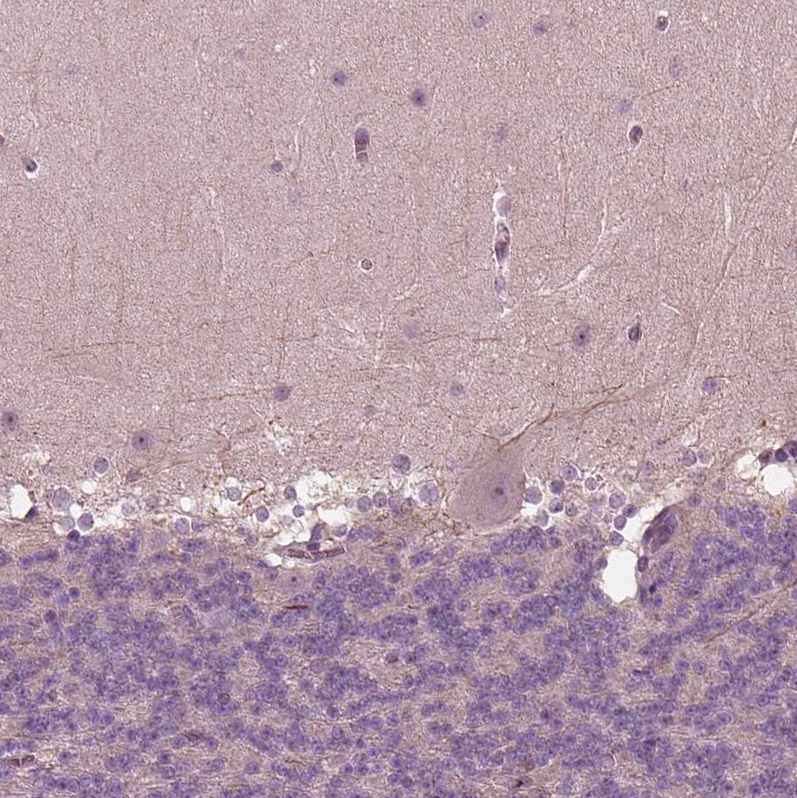

Immunohistochemical staining of human hypothalamus shows moderate cytoplasmic positivity in a subset of neurons.